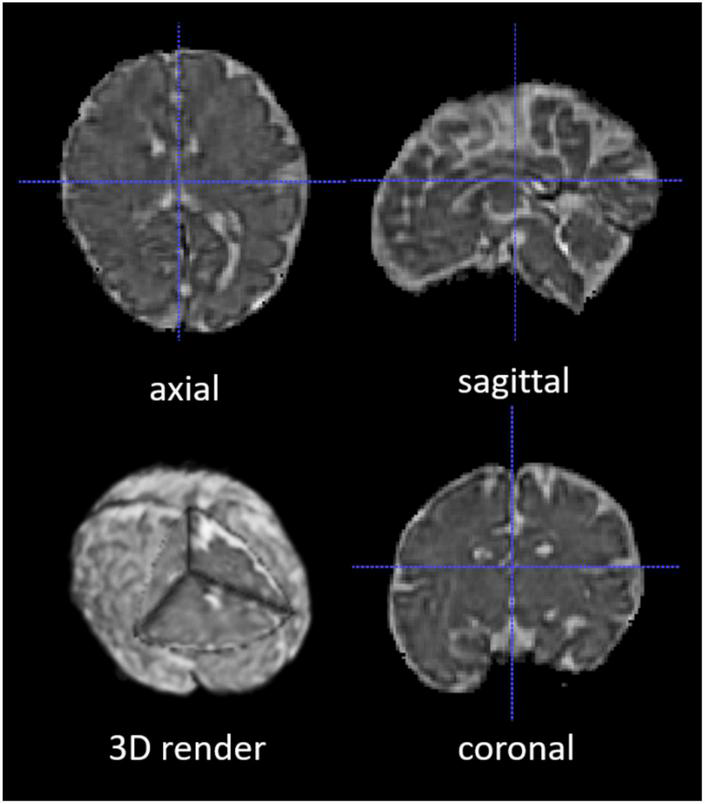

The 2D fetal brain masks of the stacks of the original fetal brain MR images were automatically segmented using NiftyMIC in the axial, coronal, and sagittal image planes. For the NiftyMIC volumetric reconstruction algorithm to perform optimally, the 2D auto-masks were manually adjusted using ITK-SNAP for the over- and under-estimations of fetal brain tissue by the NiftyMIC segmentation algorithm. The volumetric reconstruction process was performed on all 26 scans from the 21 total participants. On a total of 25 scans from 20 participants were 2D masks (96%) successfully reconstructed into 3D space (Figure 4). One participant’s data, from the total of 21 participants, was excluded due to a complete failure of the fetal brain segmentation and volumetric reconstruction routine. Once reconstructed, the image dimensions were X = 122, Y = 127, Z = 103 and the voxel size was 1 mm3.

FIGURE 4

A segmented and volumetrically reconstructed fetal brain image using NiftyMIC. The original 2D slices of fetal MR images were automatically segmented and manually adjusted for fetal brain 2D masks. Then the 2D slices and 2D brain masks were reconstructed into 3D volumes and 3D masks with motion correction. This figure shows an example of the skull-stripped, orientation-adjusted 3D fetal brain volumes in axial, sagittal, coronal, and 3D-rendered views.